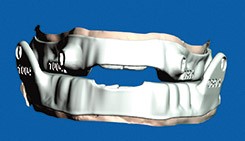

Filière numérique, protocole Phase initiale d’acquisition et de traitement des données natives (segmentation)Elle est enclenchée une fois terminée la préparation...